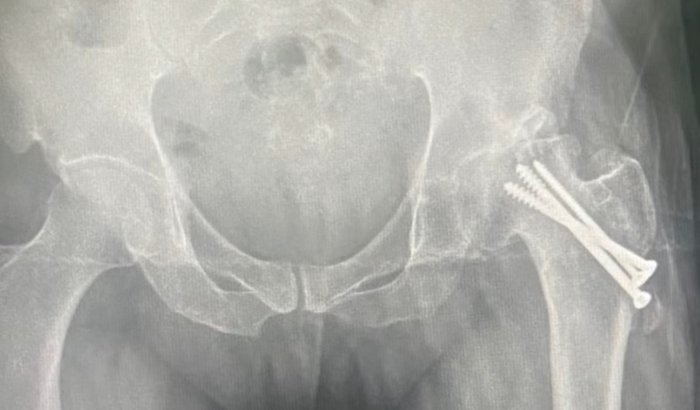

Vaquinha solidária em prol de Jessé Reis

Saúde / Tratamentos

IrecêI